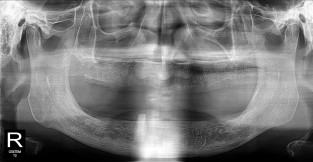

하악

치료기간 : 2021-11-30 ~ 2022-07-13

1. 상기 x-ray 이미지 모두 동일한 해당 의료기관에서 진료한 환자입니다.

2. 상기 x-ray 이미지 모두 동일 인물의 것입니다.

3. 치료 전 이미지는 2021-11-30에 촬영했으며, 치료 후 이미지는 2022-07-13에 촬영하였습니다.

4. 상기 x-ray 이미지 모두 동일 조건에서 환자분의 동의를 받아촬영되었습니다.

* 임플란트 시술은 환자분의 상태(고혈압, 당뇨 등)에 따라 부작용이 있을 수 있으니, 반드시 전문의와 상담이 필요합니다.

* 임플란트 수술 부작용

: 수술 후 출혈, 교합, 통증, 붓기, 염증 등의 문제점이 발생할 수 있습니다.)